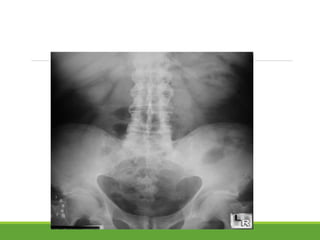

Sacroiliitis:

earliest changes blurring of the cortical margins of the subchondral

bone

followed by erosions and sclerosis.

Progression of the erosions leads to "pseudowidening" of the joint

space

as fibrous and bony ankylosis supervene, the joint space becomes

obliterated

Radiological grading of Sacroilitis

New York criteria (10)

grade 0 : normal

grade I : some blurring of the joint margins - suspicious

grade II : minimal sclerosis with some erosion

grade III :

◦ definite sclerosis on both sides of joint

◦ severe erosions with widening of joint space + / - some ankylosis

grade IV : complete ankylosis